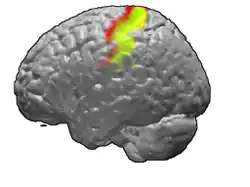

Brodmann areas 3, 1 and 2 of human brain. Brodmann area 3 is in red, area 1 in green, and area 2 in yellow. | |

The primary somatosensory cortex was initially defined from surface stimulation studies of Wilder Penfield, and parallel surface potential studies of Bard, Woolsey, and Marshall. Although initially defined to be roughly the same as Brodmann areas 3, 1 and 2, more recent work by Kaas has suggested that for homogeny with other sensory fields only area 3 should be referred to as "primary somatosensory cortex", as it receives the bulk of the thalamocortical projections from the sensory input fields.

The postcentral gyrus includes Brodmann areas 1, 2, and 3. Brodmann area 1 occupies the apex of the postcentral gyrus.